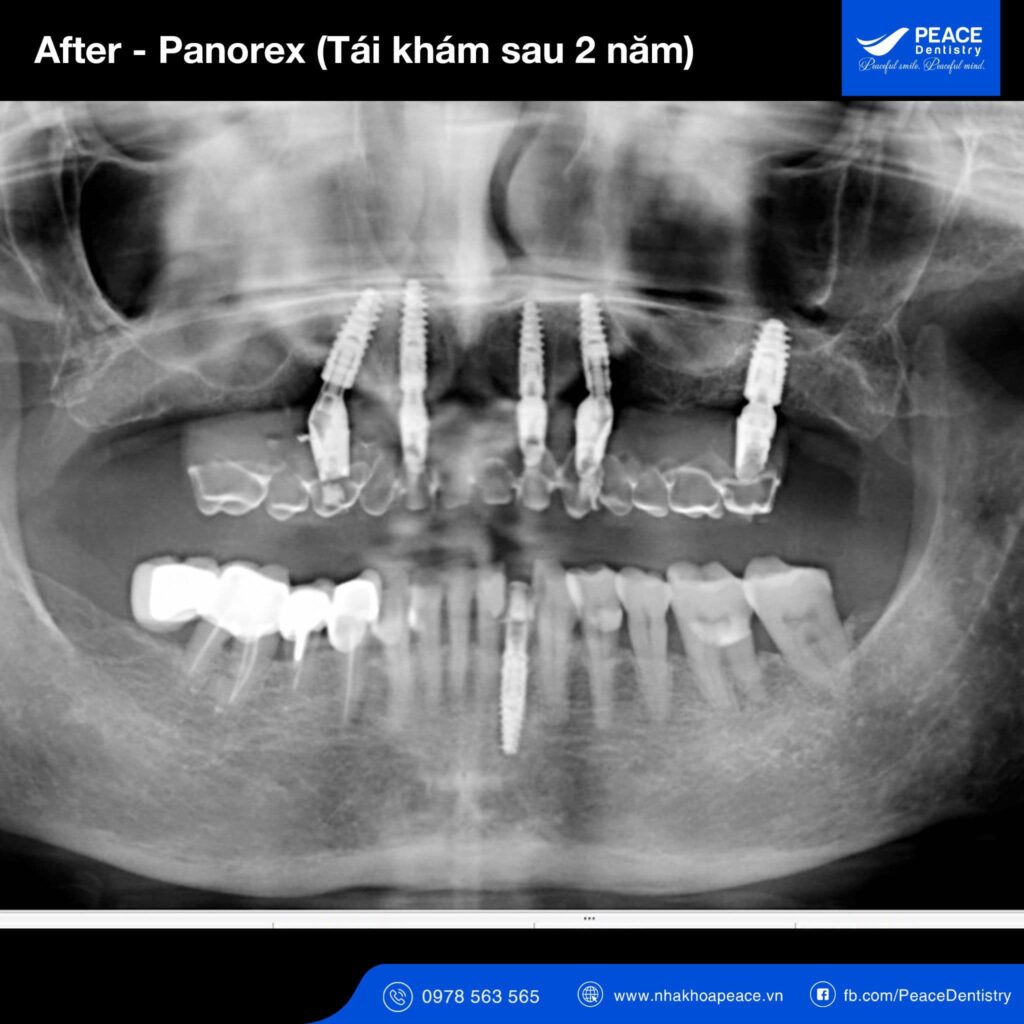

Thực tế hoạt động điều trị cấy ghép Implant tại Peace Dentistry là một minh chứng điển hình, không ít khách hàng trồng răng Implant mặc dù có bệnh tiểu đường. Và dĩ nhiên, một khi đã được bác sĩ chỉ định thì hiệu quả cũng hoàn toàn được đảm bảo.

Như vậy, có thể khẳng định: với bệnh nhân tiểu đường và nếu bệnh được kiểm soát tốt thì việc cấy ghép implant hoàn toàn có thể mang lại hiệu quả cao. Và đây không phải là 1 ca lâm sàng cá biệt mà thực tế là tất cả các trường hợp tương tự (có bệnh tiểu đường nhưng đủ điều kiện chỉ định Implant) khi cấy ghép Implant đều cho hiệu quả cao.